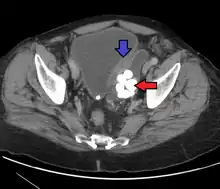

_at_trigone.jpg.webp) Histopathology of urothelial carcinoma of the urinary bladder, showing a nested pattern of invasion. Transurethral biopsy. Hematoxylin and eosin.

Histopathology of urothelial carcinoma of the urinary bladder, showing a nested pattern of invasion. Transurethral biopsy. Hematoxylin and eosin._at_trigone.jpg.webp) Histopathology of urothelial carcinoma of the urinary bladder.

Histopathology of urothelial carcinoma of the urinary bladder._at_trigone.jpg.webp) Histopathology of urothelial carcinoma of the urinary bladder.

Histopathology of urothelial carcinoma of the urinary bladder. Micrograph of urethral urothelial cell carcinoma. Hematoxylin and eosin stain.

Micrograph of urethral urothelial cell carcinoma. Hematoxylin and eosin stain.